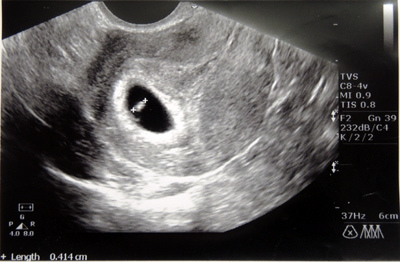

2014.10.17 6w 超音波看心跳

滿6w了!

這次回診的主要目的就是照超音波,看胚胎位置和心跳數。

超音波螢幕上,白點閃呀閃的,怎麼會這麼迷人啊?

整個大閃神的我,連檢驗師說甚麼都沒聽清楚,

大概是只有一個胚胎,大小符合週數約0.4cm,心跳數約130/分鐘。